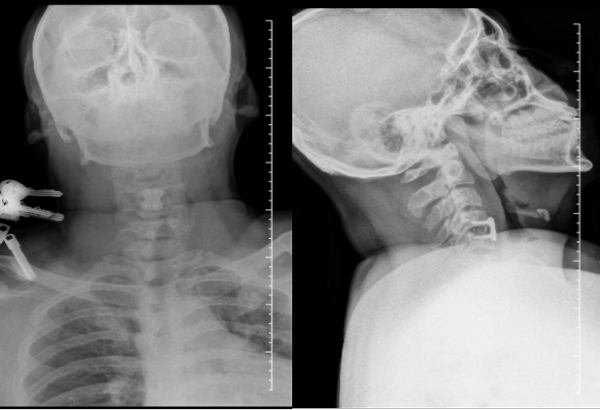

术后X线